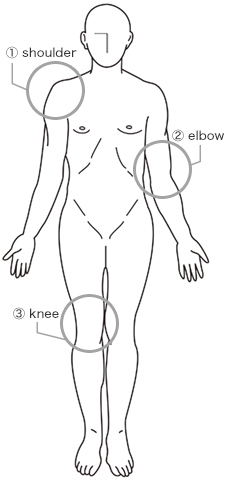

肩-shoulder-(菅谷 啓之 先生)

肘-elbow-(高橋 憲正 先生)

膝-knee-(土屋 明弘 先生)